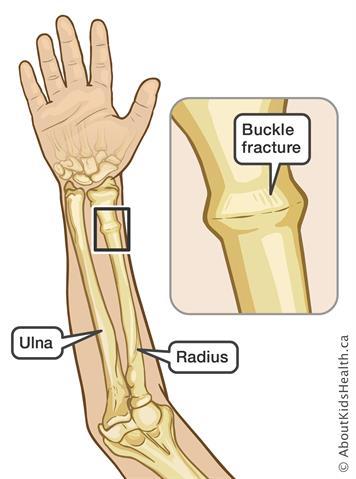

What’s Buckle’s fracture?

Buckle’s fracture

What’s that?